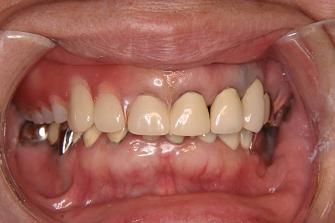

【症例 4】6歯欠損 (55才,女性)

正面上(ミラー像)

1.

術前のお口の状態です